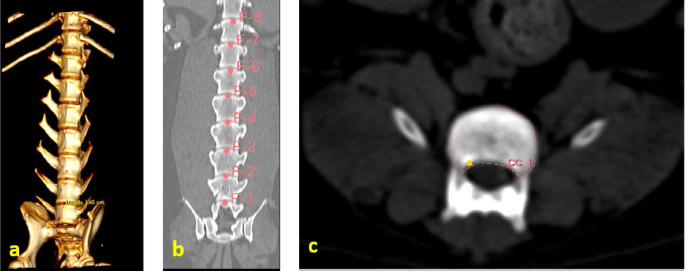

A necropsy was performed on the animal, during which the lumbar vertebrae from L1 to L7 were separated (Fig. 1a–c). The resulting segment was frozen in a refrigerator at −20°C. The segment obtained in the biomechanical study was gradually thawed to room temperature (22°C). The segment was treated, and the surrounding muscular and fatty connective tissues were separated. Each vertebra was separated, and the spinal cord was removed.

Fig. 1. (a) Canine lumbar caudo-cranial vertebrae view. (b) Canine lumbar latero-lateral vertebrae view. (c) Canine lumbar dorsoventral vertebrae view.